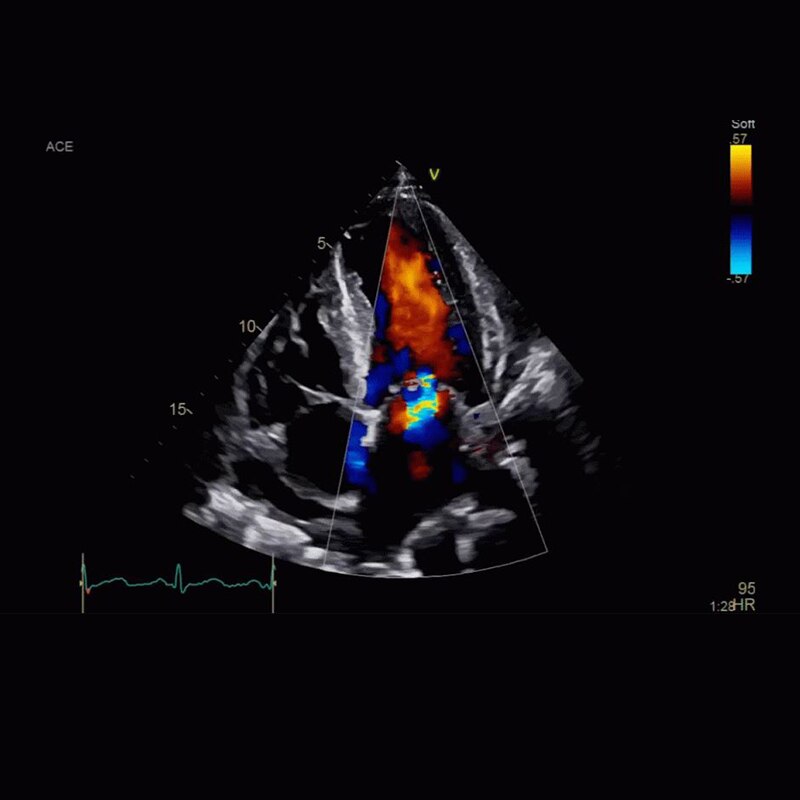

Due to the high mortality rates by the time patients are symptomatic, it is important to identify patients at risk, even when they are asymptomatic. Echocardiography can identify issues or abnormalities related to Aortic Valve structure and function.3

Vivid E95/E90/S70N

cSound™ beamforming technology for exceptional visualization quality with impressive resolution in 2D, color flow, Doppler and 4D formats.

Vivid E95

Semi-automated quantification tools.